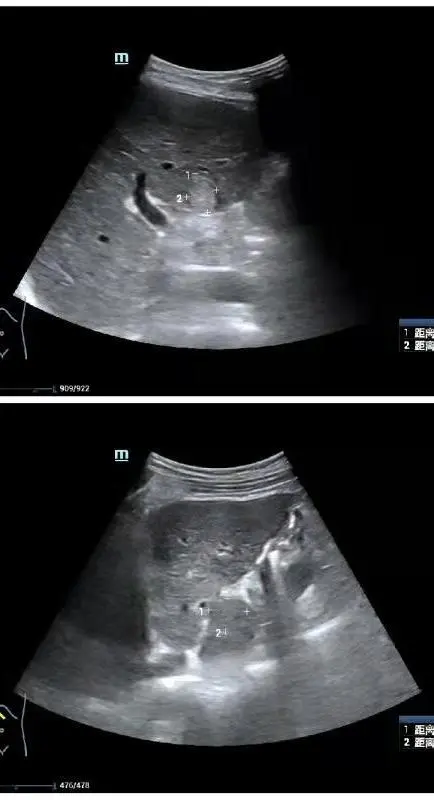

∆ 術前超聲顯示病灶位於膽囊旁和尾狀葉

∆ 消融術中